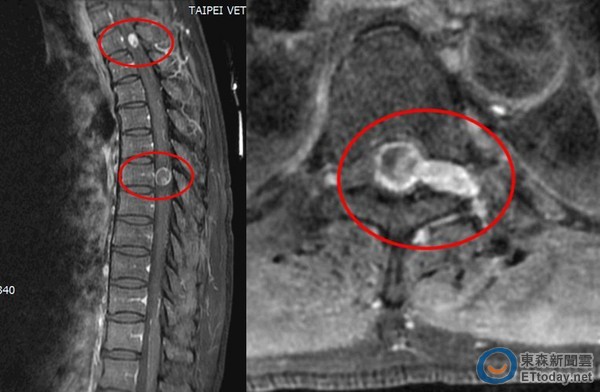

▼關先生的脊椎有2顆腫瘤,已經嚴重壓迫到神經。(圖/台北慈濟醫院提供)

關先生在慈濟醫院確診為脊椎腫瘤後,院方立即為其行手術治療。黃國烽說,關先生脊椎腫瘤的界線清楚,在解除脊髓腔內壓迫、打開硬膜,耗時6個多小時切除2顆腫瘤後,便暫時解除壓迫危機。由於發現得時間尚早,關先生術後恢復情況良好,不僅恢復體力、開車走路,更在近日重返工作崗位,重新巡視山林。